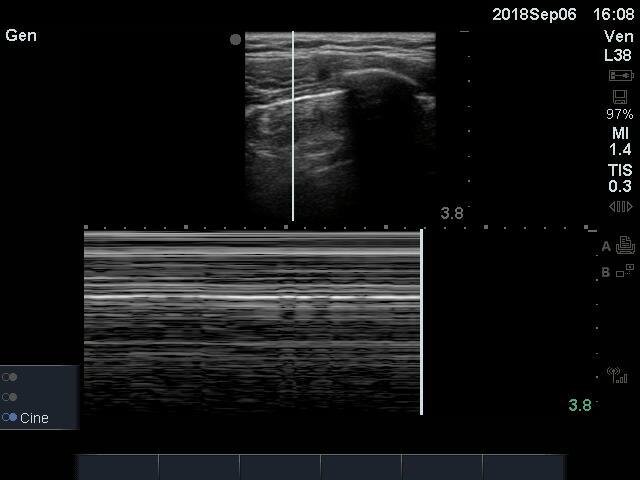

The above images are of the left anterior chest and were acquired using the linear probe.  The curvilinear probe may also be used for lung ultrasound.

In the video, we see a pleural line that is static without the classic “sliding.”  In an ultrasound of a healthy normal lung, we should see a to-and-fro movement or shimmering of the pleural line. This has often been described as ants on a log. In the case of pneumothorax, however, there is air between the visceral and parietal pleura that prevents visualizing of the visceral pleura and inhibits lung sliding.

In the still image of M-mode, we see a pattern of horizontal lines above and below the pleura.  This pattern is referred to “barcode” sign, and is indicative of a lack of movement.